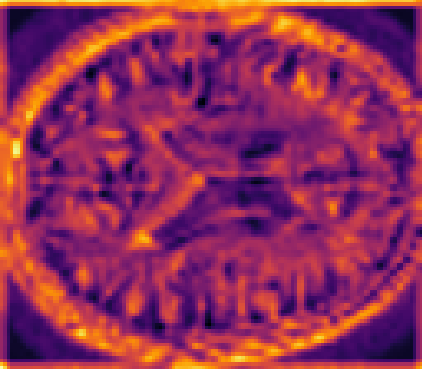

Looking at sample synthetic PET images in Fig. 3, it can be seen that all of the models are able to make reasonable predictions. The outputs of the U-PET and U-PET (no att.) look very similar and are smoothed compared to the input. The pix2pix predicts more details, which seem to be important for the discriminator. However, even though this model has finer predictions, the intensity values are worse compared to the U-PET and U-PET (no att.) as seen in Fig. 2; an example is given in Fig. 3 in the second row.

From a clinical perspective, the synthetic generated PET show a smoother version of the real PET images but keep the same pattern of FDG uptake, especially, hypometabolism in the respective brain areas. This backs up our hypothesis, that MRI contains information that correlates with the functional information of PET images. Moreover, the synthetic PET could be used as complementary visualization for physicians beyond the task of classification.

In Fig. 4, the attention maps of the U-PET are shown for multiple examples. On the one hand, the attention map of the skip connection (AttMap skip) highlights details of the brain structure, which is in agreement with the assumption that the network has to transform the specific structures of the MRI scan into the PET modality. On the other hand, the attention gates used for the classification task rather focus on more specific regions. One can observe a trend that the attention maps used for classification tend to highlight regions which have a low uptake in the PET. Since areas with a lower uptake in the PET correspond to areas with lower functional activity (hypometabolism), this focus area of the network seems reasonable with respect to the classification task.